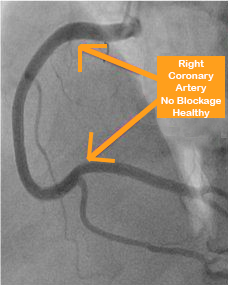

Coronary Angiogram over time with whole foods based diet

There are three arteries that run over the surface of the heart and supply it with blood.

There is one artery on the right side, and two arteries on the left side. The one on the right is known as the right coronary. On the left side, which is the main side, we have the left anterior descending (LAD) that runs down the front of the heart and supplies the front and main wall, and then the left circumflex that supplies the sidewall. If you look carefully, a major artery called the left main artery supplies the LAD and the circumflex.